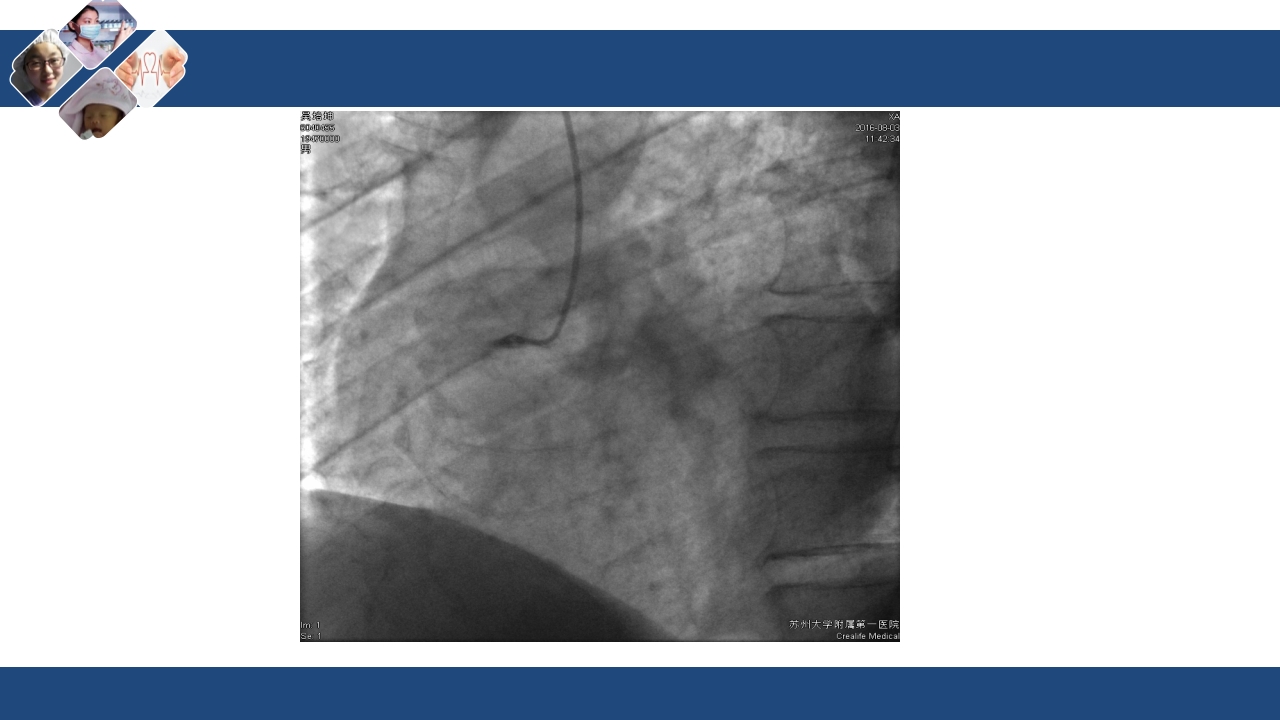

心肌梗死合并心源性休克 医院:xxx 时间:xxx 休克 是由于各种原因导致的急性循环障碍,使周围组织血流 灌注量严重不足(微循环障碍),以致各重要生命器官机 能代谢发生严重障碍的全身性病理生理过程。 休克的病因: 心源性 低血容量性 感染性 过敏性 神经内分泌性 创伤性 休克的病因: 心源性 低血容量性 感染性 过敏性 神经内分泌性 创伤性 心源性休克(cardiogenic shock) 心源性休克系指由 心室泵功能损害而 导致的休克综合征, 是心泵衰竭的极期 表现。 由于心排血功能衰 竭,不能维持其最 低限度的心输出量, 导致①血压下降, ②重要脏器和组织 供血不足,引起③ 全身性微循环功能 障碍 从而出现一系列缺 血、缺氧、代谢障 碍及重要脏器损害 为特征的病理生理 过程。...